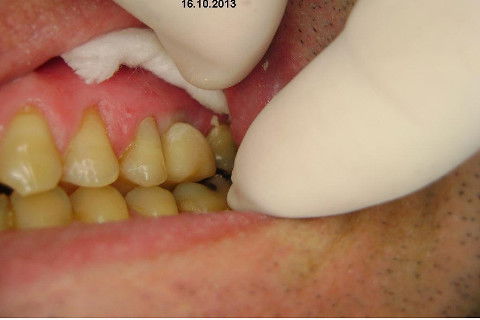

Instalação de um implante em região do 26. Utilizamos um implante cone morse Alvim Neodent 4.3 X 11,5. Foi uma cirurgia muito rápída e minimamente traumática, sem retalho e sutura.

Fotos do caso